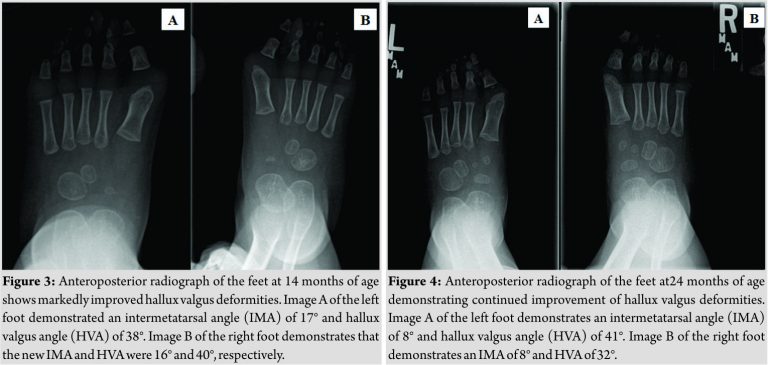

The apparent duplication of the cartilaginous metatarsal head favored a diagnosis of polydactyly. Treatment was offered consisting of splinting of the feet and lower extremities with close follow-up and, if there was no improvement overtime, excision of the redundant metatarsal head with closing wedge osteotomy of the distal metatarsal. The family declined any treatment including bracing. At 14 months of age, the subject was pulling to stand and cruising. The overall appearance of his foot had improved with a drastic decrease in overlap of the second and first toe. He had no difficulty with shoeing or other clinical problems. Imaging demonstrated an overall improvement in alignment. The right IMA had improved to 16°with an HVA of 40°. The left IMA hadactually worsened radiographically to 17°, but the HVA had improved to 38°(Fig. 3).

At 26 months of age, the subject remained asymptomatic. Imaging demonstrated improved alignment from the previous visit with a normal IMA bilaterally of 8°. His HVA on the right was 32°and 41° on the left, which was consistent with prior measurements (Fig. 4). He was able to keep up with other children without difficulty and had no problems with shoe wear. He continued to have overlap of the first and second toe (Fig. 5), but he had full, painless range of motion.